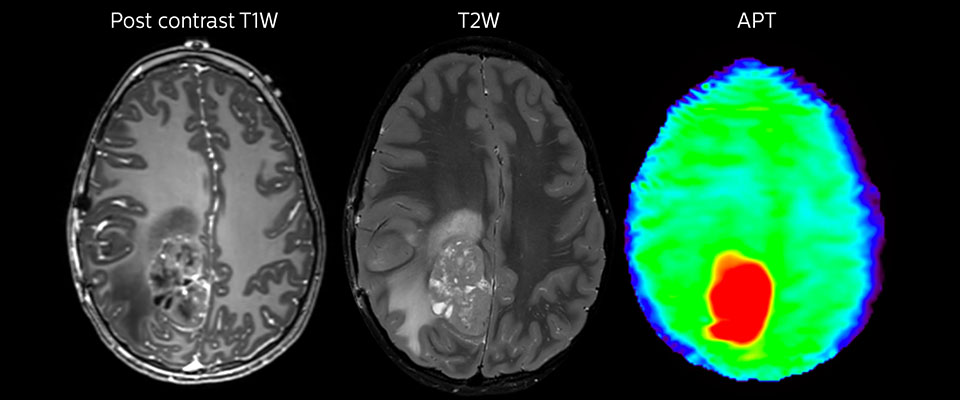

APT imaging of high-grade tumor

Tumor evaluation in a 1-year-old child with medulloblastoma. This aggressive tumor type is very solid and homogeneous. The high APT signal corresponds with the post-contrast image of this high-grade tumor.

APT may be a powerful addition to grade tumors with MRI